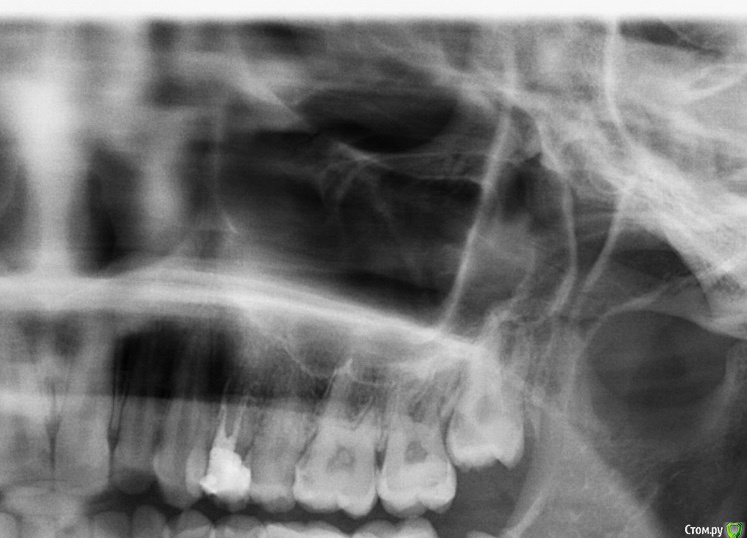

Marialalala Опубликовано 22 марта, 2020 Поделиться Опубликовано 22 марта, 2020 Здравствуйте, 4 дня назад удалили верхний зуб мудрости, удалили быстро сам зуб, но потом ещё вычищали отломившейся корень, по ходу делали несколько прицельных снимков, врач сказал, что все чисто, в конце была проведена «носо-ротовая» проба, оказалась перфорация, врач положил губку альвостаз и ушил лунку наглухо, выписал антибиотик, капли гормональные и т д, пришла на повторный осмотр через 2 дня, врач осмотрел лунку и сказал, что все хорошо и должно быть все хорошо, но если вдруг появятся симптомы... (одонтогенного гайморита), то конечно прийти к нему. Мне необходимо далее продолжать лечение зубов, поэтому как раз сегодня сделала панорамный снимок. Скажите, все ли хорошо в области удаленного зуба по снимку? Нет ли отломков зуба в пазухе, воспаления? Очень переживаю, так как есть знакомый, оказавшийся после удаления зуба в члх. Самочувствие хорошее, температуры нет, болевых ощущений нет. Два файла прикрепила - с зубом (того года ) и на 4 день после удаления Ссылка на комментарий